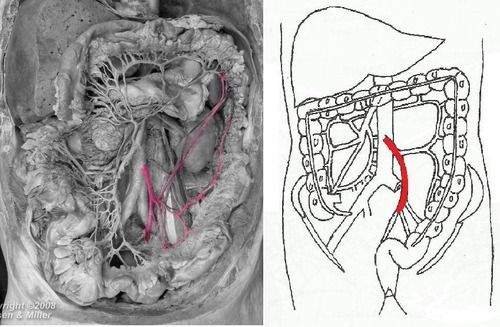

Superior Mesenteric Artery

Vasa Recta

descends to the ileocecal junction

Ileocolic Artery

supplies the ascending colon

Right Colic Artery

supplies the transverse colon

Middle Colic Artery

Marginal Artery

Inferior Mesenteric Artery

supplies descending colon

Left Colic Artery

supplies the rectum and upper part of the anal canal

Superior Rectal Artery

supplies the sigmoid colon

Sigmoid Arteries